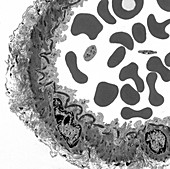

12420843 - Artery, TEM

12302981 - Artery, TEM